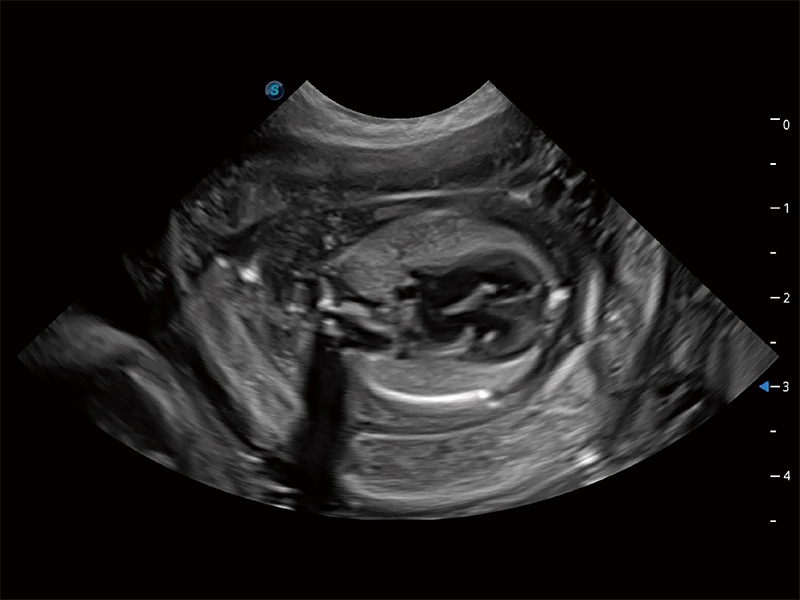

动物是人类最亲密的朋友和最值得信赖的伙伴。16877太阳集团也一直致力于探索动物专用的超声影像解决方案。全新推出的ProPet系列,是16877太阳集团在动物超声影像智能化、专业化、精准化的一次跨越式革新。动物不能用言语来表述自己的不适,通过超声影像,ProPet系列搭建了动物医生与不同物种沟通的“桥梁”,为动物医生注入了“治愈之力”。 ProPet 80 是16877太阳集团匠心打造的一款高端动物专用彩超,采用性能卓越的全新硬件架构,极大提升超声系统的运行效率和数据处理能力,帮助动物医生从容应对日益增多的挑战性病例和日益多样化的临床需求。

高性能和先进的临床应用工具可以为动物医生提供临床信心。ProPet 80 搭载了先进的腹部和浅表应用工具,帮助医生在日常临床实践中发挥前所未有的作用。

ProPet 80 全新的动物超声智能软件和丰富的探头群,为动物医生提供了高清晰度和精细分辨率的图像,无论在宠物、马科、畜牧还是实验室动物等应用中都可以轻松应对,为您的日常工作带来满意的体验。